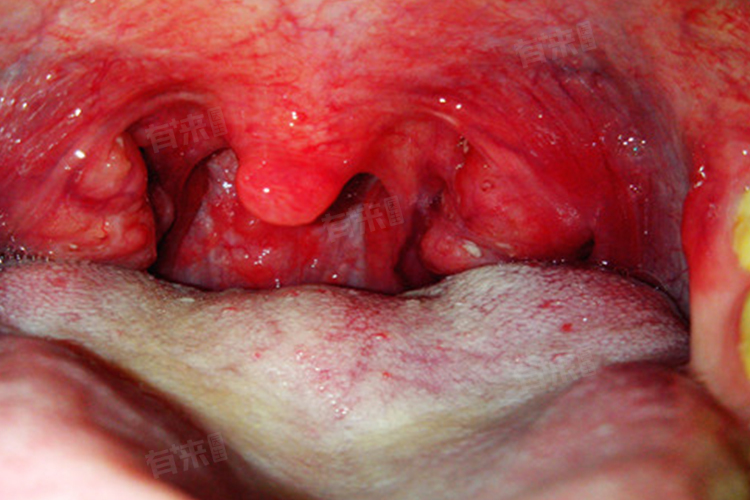

3、喉咙炎症:包括急性咽炎、慢性咽炎急性发作以及扁桃体炎等,也是导致喉咙刺痛的常见原因。这些炎症多由细菌或病毒感染引起,会导致喉咙黏膜充血、肿胀,甚至糜烂,从而产生刺痛感。患者还可能伴有咳嗽、咳痰、喉咙干燥、异物感等症状。